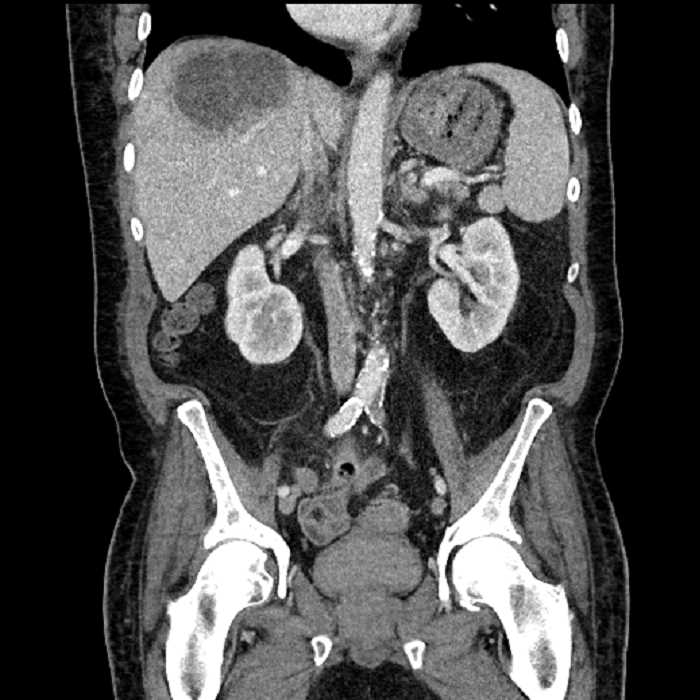

Age: 63

Sex: Male

Indication: Abdominal pain

• Large fluid density structure in hepatic segments 7 and 8 measuring 10 x 7 x 7 cm with internal septation and circumferential ill-defined low density compatible with edema

• Peripherally enhancing subcapsular collections along the anterior margin of the left hepatic lobe measuring 3 x 1 cm and 2 x 1 cm

• Clearly marginated fluid density structure in segment 7 and several other scattered tiny hypodensities, which likely represent cysts

• Hepatic abscess

Acute sigmoid diverticulitis complicated by a small contained perforation and a large abscess in the right hepatic lobe. Additional small subcapsular abscesses along the anterior margin of the left hepatic lobe.

Additionally, loss of the normal fat plane between the peridiverticular collection and adjacent thickened loops of small bowel raises the potential for an enterocolonic fistula.

• The classic CT imaging appearance is a double target sign with internal low density surrounded by an internal enhancing rim (capsule) and a low density external rim (edema)

Hepatic abscess showing the double target sign with low density internally surrounded by a thin inner enhancing rim (red arrow) and ill-defined outer low density rim (yellow arrow). Blue arrow indicates an internal septation. Red arrows: additional smaller subcapsular abscesses. Red arrow: focal contained perforation associated with diverticulitis.